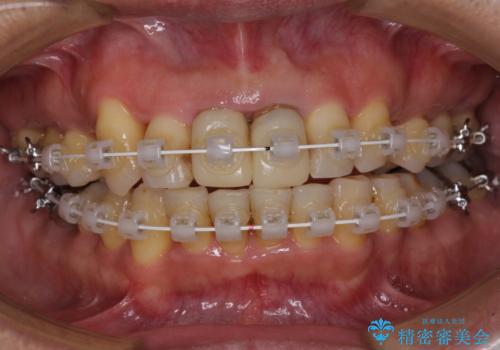

八重歯と突出感を改善 ワイヤー装置での矯正治療

- 八重歯を気にして来院された患者様です。

上顎前歯の突出感と右上の八重歯を気にされていたので、上顎左右の第一小臼歯2本を抜歯し、ワイヤー装置にて矯正治療を行うこととしました。

上顎前歯に装着されていた保険診療の前歯は見た目が気になるとのことであったので、矯正治療後にオールセラミッククラウンにて補綴治療を行うこととしました。

食いしばりにより奥歯がすり減っており、咬み合わせが定まるまで時間がかかりましたが、整った口もに仕上がりました。